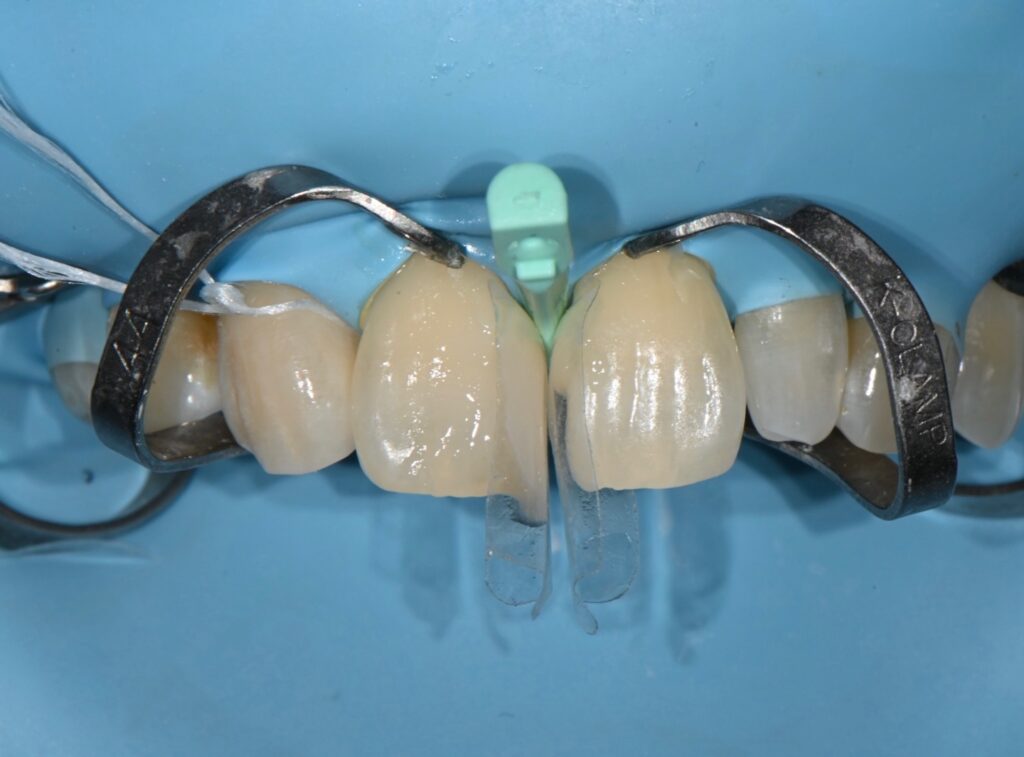

적절한 바이오클리어 쉘의 선택

출처 입력

그리고 다이아스테마 즉 정중이개 치료에서 필수는

바이오클리어라는 shell이 필수인데요

적절할 크기와 모양을 선택해야

자연스러운 치아 모양이 만들어 집니다

1차로 적절한 바이오 클리어를 선택하고

자기에 맞는 색상의 레진 선택